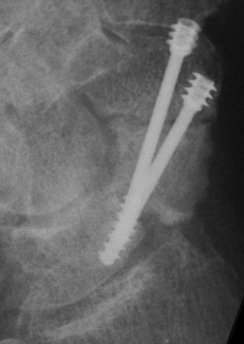

Case 4. Nonunion with a graft and screws placed in both directions from a single palmar approach, hyperextending the wrist for the proximal entry...

and with the graft:

and with consolidation,